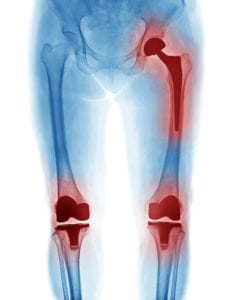

Joint Replacement Surgery

FAQs About Knee Replacement Surgery

More than 600,000 knee replacement surgeries are performed every year in the United States. This surgery aims to relieve painful and disabling symptoms in the knee – usually due to arthritis – and to restore knee function. Advancements are continually being made in the materials and techniques Read More

Joint Revision: Why Is It Needed?

Total joint replacement surgery is becoming increasingly popular among people of virtually all ages, with more than 1 million procedures being performed in the U.S. every year. Joint replacement surgery involves removing and replacing certain parts of an arthritic or damaged joint with an artificial Read More